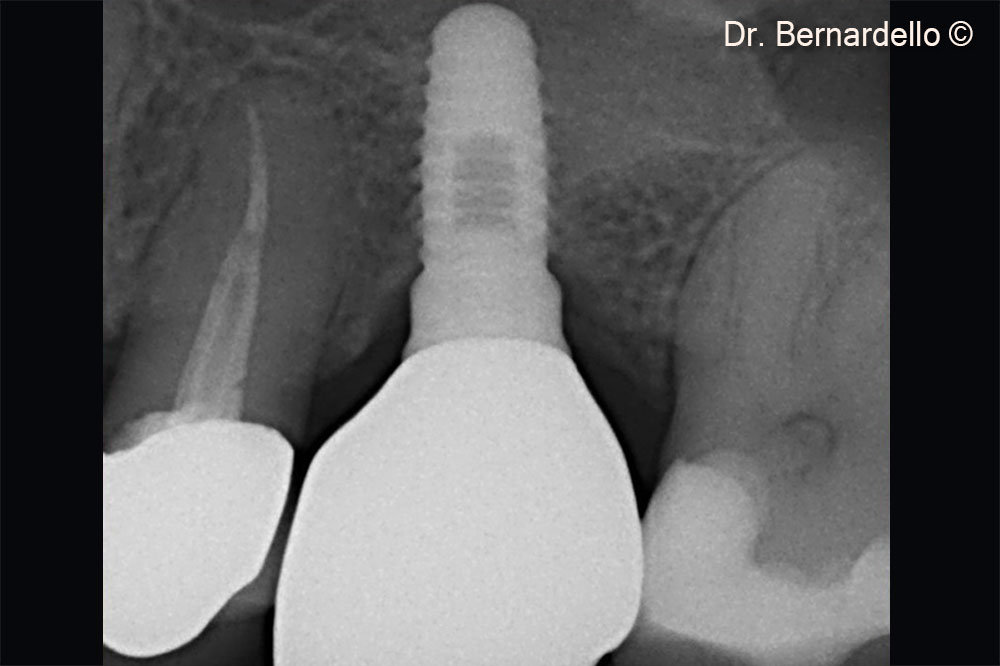

Immediate final restoration

Above the apex on the implant, it is possible to see a thin layer of cortical bone